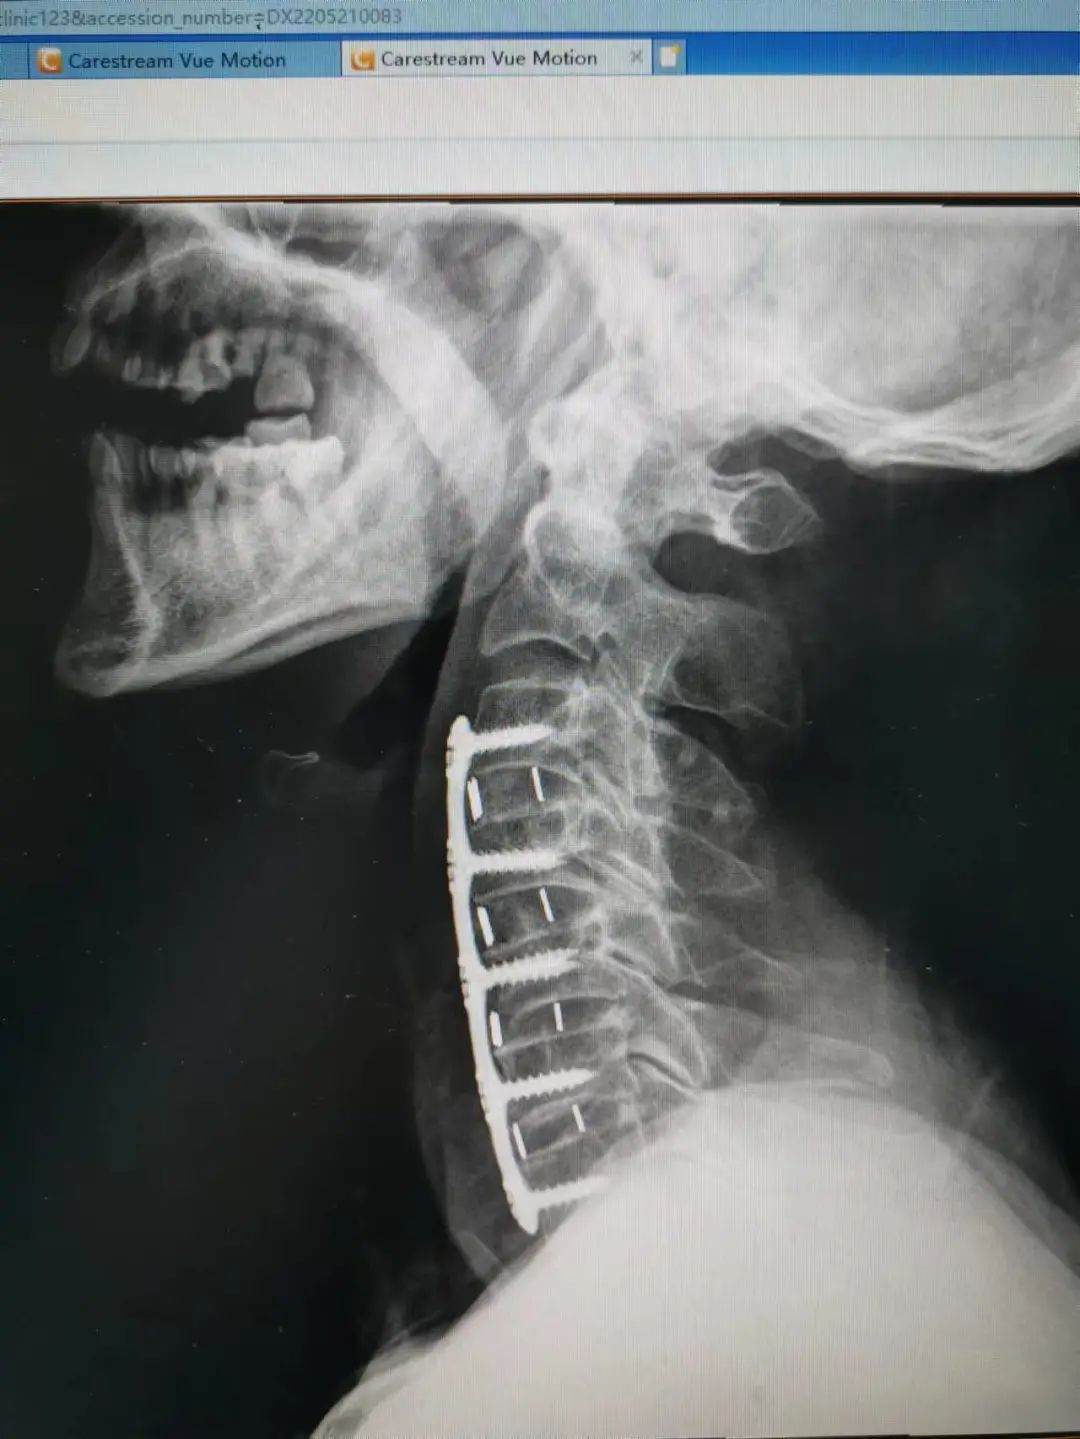

杨先生术后拍片

由于杨先生的病情严重,需住院治疗。杨先生入院后,泸州市中医医院骨伤二科科主任杨陈一制定了手术计划,决定脊髓型颈椎病的手术从前路切开减压,颈3/4 、颈4/5、 颈5/6、 颈6/7椎间盘切除,椎间融合,钢板内固定术手术,而腰椎管狭窄症经后路切开减压,腰3/4、腰4/5椎同盘动除,椎间融合、钉棒系统内固定术。